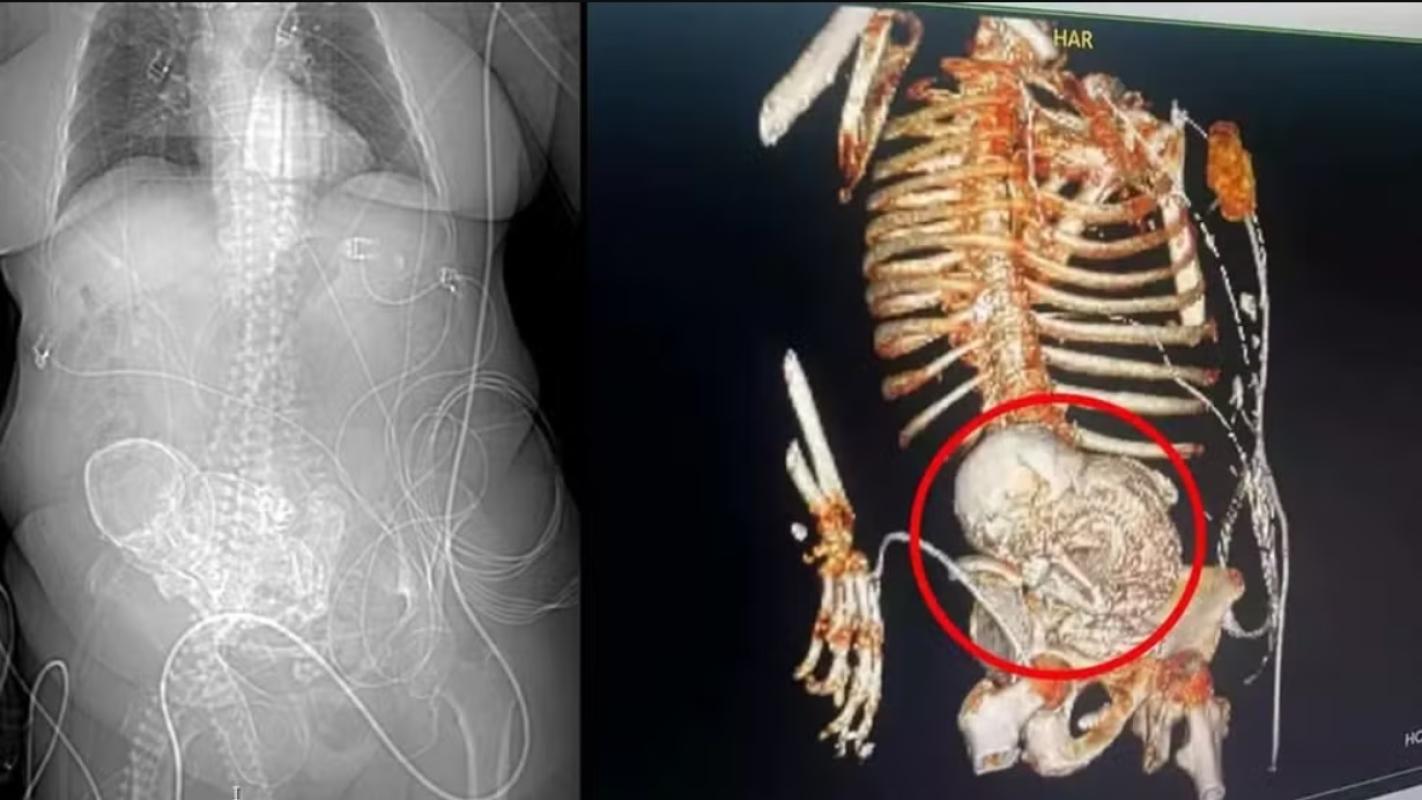

Bajo ese contextos, los médicos le hicieron una tomografía para saber qué es lo que estaba pasando en su cuerpo. Cuando obtuvieron los resultados, no podían creer que la mujer tenía un feto calcificado en su interior.

Los expertos calcularon que la mujer cargó con el también llamado "bebé de piedra" desde su último embarazo, entre hace 30 y 40 años atrás, por lo que el equipo médico de urgencias procedió a realizar la extracción quirúrgica del feto con la intención de "controlar la grave infección que sufría la mujer y que amenazaba con su vida", según contó El Mundo.